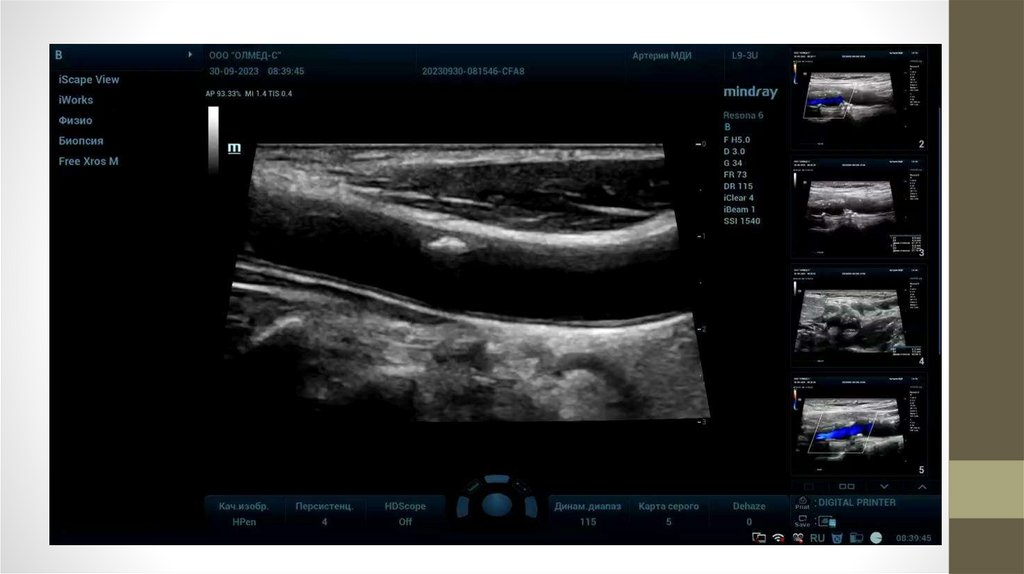

Изменения в сосудах

Атеросклеротические бляшки – наложения на внутренней стенке сосуда (артерии)

холестерина и кальция.

При увеличении бляшки возникает нарушение кровотока по сосуду вплоть до полного

прекращения.

Обычно возникают в пожилом возрасте, но нередко обнаруживаются и у молодых людей.

Причины:

- курение (в том числе электронных сигарет)

- неправильное питание (высококалорийная,

жирная пища - чипсы, гамбургеры, шашлыки,

из напитков - сладкая газировка, энергетики)

- малоподвижный образ жизни

(отсутствие регулярных занятий спортом)

- повышенное артериальное давление